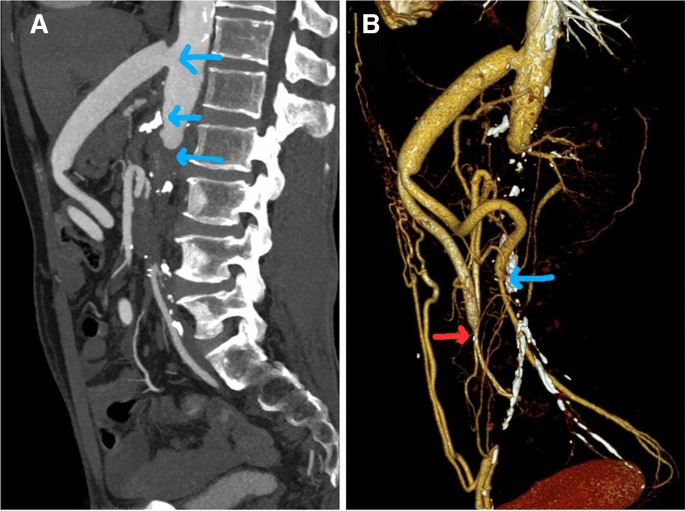

Chụp cắt lớp vi tính mạch máu (CT Angiography): Tiêu chuẩn vàng để phát hiện vị trí, mức độ tách động mạch.